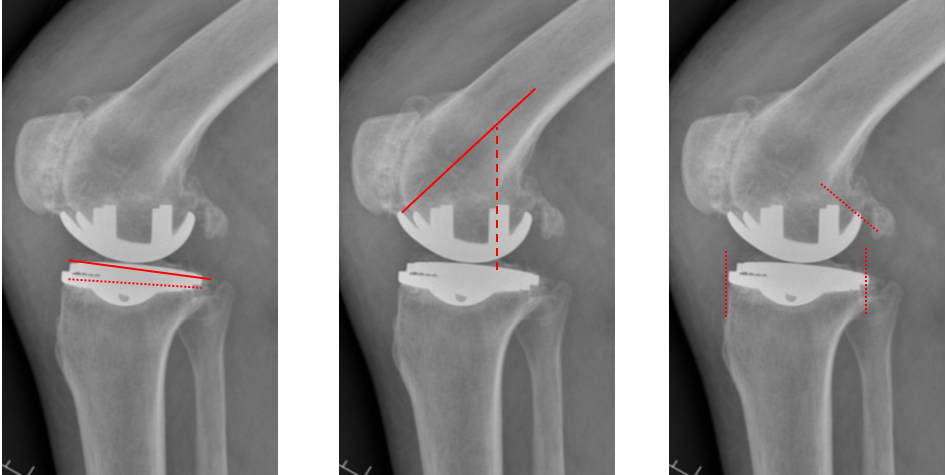

正位片标准胫骨和股骨假体位置

AP位假体位置:胫骨假体无明显内外翻,与胫骨轴线垂直,内侧缘与胫骨平台内侧缘齐平; 股骨假体长轴与胫骨假体垂直,中线一致。

胫骨假体3°内翻

AP位胫骨与股骨假体位置:胫骨假体内翻3°,股骨假体中轴线与胫骨假体垂直。

胫骨假体内侧悬挂

AP位胫骨假体位置:胫骨假体内侧悬挂>2mm。

股骨假体偏内放置

AP位胫骨与股骨假体位置:股骨假体轻度内翻,中轴线与胫骨假体中线不一致,偏内侧。

胫骨假体偏大,且后倾不足

侧位胫骨假体位置:胫骨假体后侧悬挂>2mm,后倾2°。

胫骨假体后倾角度大

侧位片胫骨假体位置:胫骨假体后倾12°,前后缘齐平 。